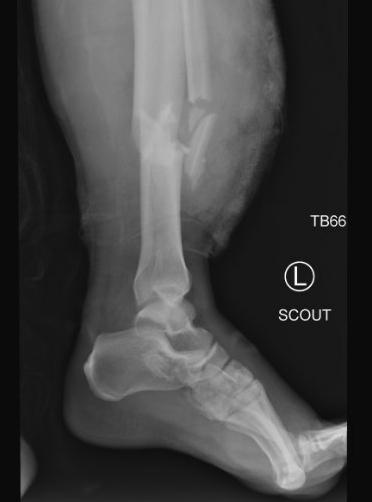

A 34-year-old male driving a commercial van was involved in a high-speed, head-on motor vehicle crash approximately 75 miles from the closest Level 1 Trauma Center. There was extensive damage to the front end of the vehicle and both of the patient’s legs were badly trapped. Multiple agencies responded to the scene, including ground emergency medical services (EMS), fire agencies, air medical services, and law enforcement. While the fire crews quickly began extricating the patient from the wreckage, the EMS providers were able to reach the patient within the vehicle to begin treatment. This included the application of tourniquets to both legs. Immediately recognizing this was going to be a prolonged extrication process for a patient who was critically injured, EMS providers contacted an emergency medicine (EM) physician from the closest local hospital. The physician on-call happened to be a paramedic and the county EMS medical director. Upon receiving

report of the patient, the EM provider responded to the scene. En-route, the EM physician contacted the Kessler Trauma Center’s on-call Trauma Surgeon to report the event and obtain further guidance. During the extrication process, the prehospital providers administered blood and plasma transfusions and gave tranexamic acid (TXA), a medication used to help clot blood when there is concern for major bleeding. A breathing tube was also placed to protect the patient’s airway. Once

extricated from the vehicle (after about two hours), the patient was flown to the Kessler Trauma Center in Rochester.

The Trauma Center was notified by Helicopter EMS that the patient was en-route and critically ill, which prompted a Level 1 (highest tier) trauma activation. With this, a multidisciplinary trauma team assembled in the trauma resuscitation area of the emergency department to prepare for this patient’s arrival. The team, when activated, includes the attending trauma surgeon, attending EM physician, trauma surgery residents, an emergency medicine resident, anesthesiologist, respiratory therapist, and specially trained nurses. In this case, as in many others, our orthopedic surgery and orthopedic spine services were also present in the trauma bay prior to patient arrival.

The patient was immediately examined and found to have a very fast heart rate and very low blood pressure (indicating major blood loss) along with significant wounds and open fractures to both of his legs. The patient was transfused with whole blood, and the massive transfusion protocol was activated to allow for the transfusion of additional blood as needed to compensate for the extensive blood loss that occurred at the scene of injury. Preliminary imaging in the trauma resuscitation unit showed multiple left and right rib fractures and a severe pelvic fracture, likely resulting in major bleeding. Our trauma and orthopedic surgery teams immediately placed a pelvic binder to control

pelvic bleeding and then washed out the wounds to both legs to help prevent early infection. Once the patient was stabilized, he was brought to the CT scanner for further imaging.

The injuries found on CT scans included a spleen laceration, a large lung bruise, extensive fractures throughout both legs, multiple extensive pelvic fractures, arterial bleeding in the pelvis, multiple spine fractures, and a traumatic brain injury. Due to the active bleeding from the pelvic fracture, it was determined that the patient would benefit from an urgent interventional radiology (IR) procedure to control the bleeding from inside the pelvic blood vessel. The Critical Embolization Response Team (CERT) was activated.

Prior to IR, orthopedic surgery placed both patient’s legs in traction devices to realign the broken bones and keep them stabilized (to prevent bleeding and pain) until the patient was ultimately able to

proceed to the operating room with Orthopedic Surgery to begin repairs of the bones in both legs and pelvis. Ultimately the injuries would require a ‘staged’ approach, meaning the legs and pelvis would need to be repaired over multiple operative procedures. The first operative procedure required two orthopedic surgery attendings due to the extent of the injuries, with one surgeon operating on the left leg and pelvis and one surgeon operating on the right leg. Between hospital day one and hospital day 17, the patient went to the operating room with orthopedics a total of seven times. The patient’s right leg underwent successful fixation. Unfortunately, the damage to the left leg was far more extensive and ultimately required amputation

which was performed without complication on hospital day 22.

The patient was placed in a cervical collar for treatment of his spinal fractures and his splenic laceration was managed non-operatively. The patient’s brain injuries were closely monitored and treated non-operatively by neurosurgery. The Physical Medicine and Rehabilitation team was also involved in patient’s care to provide neuro-recovery recommendations to optimize his recovery from his traumatic brain injuries. By hospital day four, his sedation was decreased, and he was alert and following commands. By hospital day ten, he had his breathing tube removed and was awake and alert. By hospital day 13, with the assistance of the Medical Nutrition Therapy service, the patient transitioned from tube feedings to a regular diet.